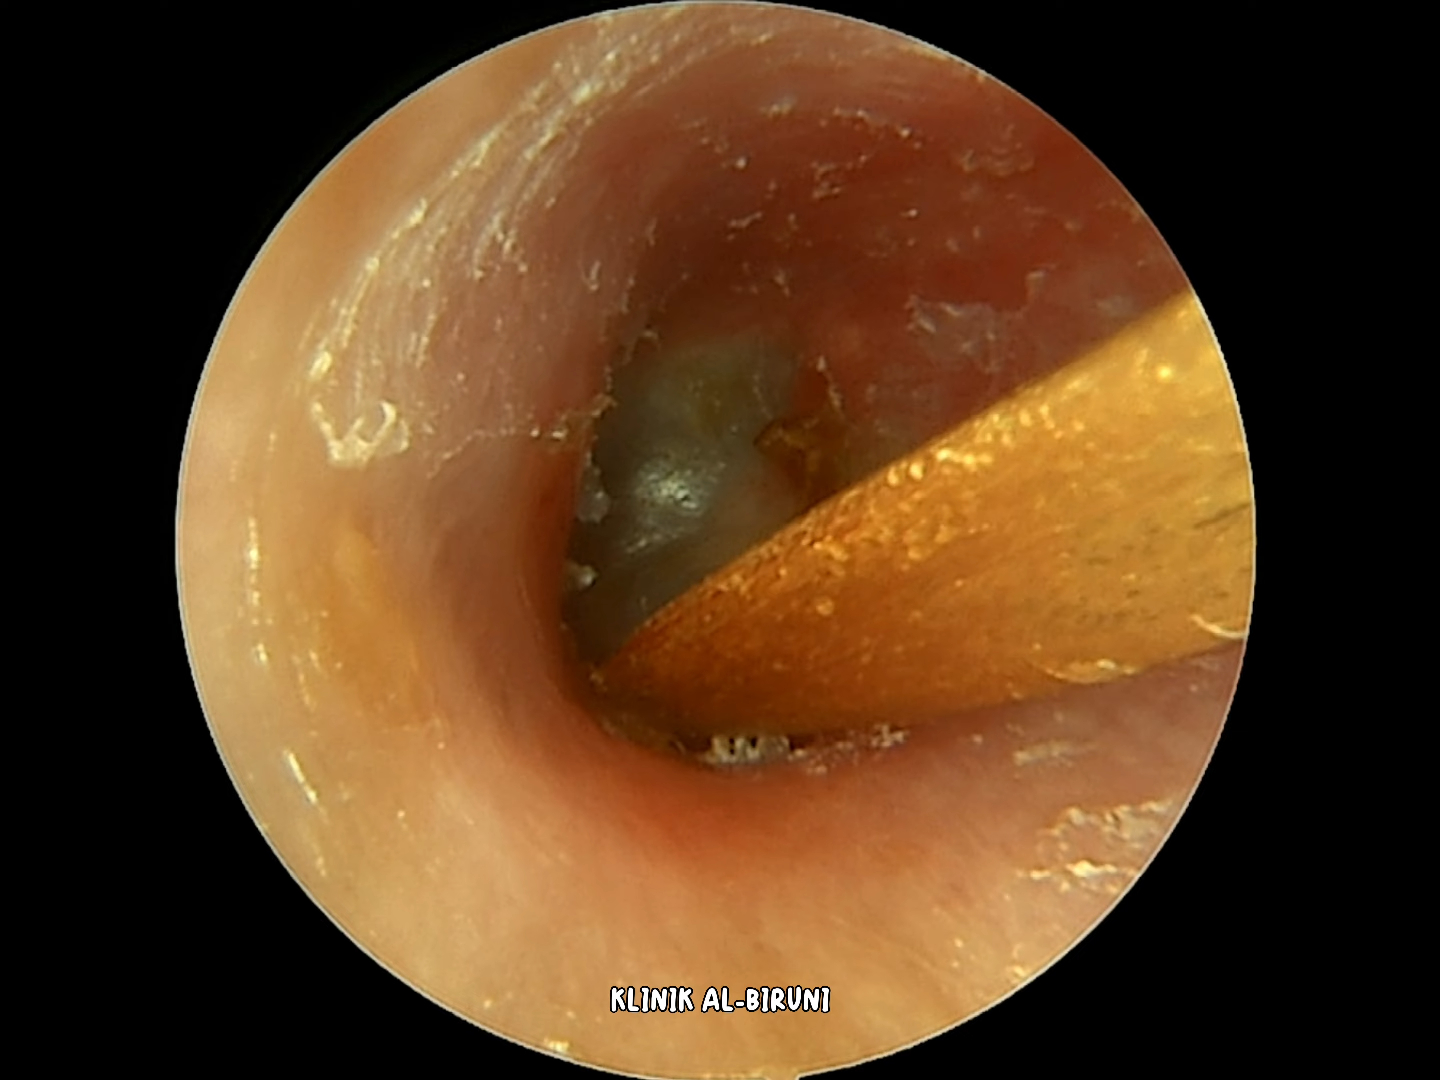

掏耳朵解压-金色结痂耳垢层已去除! (4k 60fps)

好大一块痂皮,紧紧的粘在了耳道上 把它完整的撕下来

小姐姐的耳朵;里面好大一块痂皮 把整个耳道都封住了